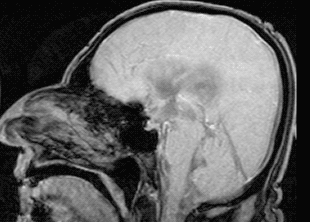

Пульсация спинномозговой жидкости в мозге человека. Во время этой пульсации и идёт очистка от "мусора"